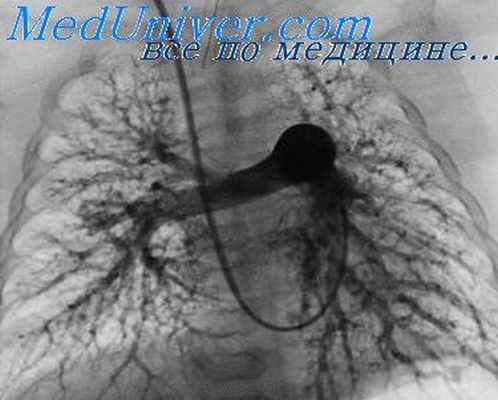

14. Ангиография

ангиопульмонография контрастирование ветвей легочной артерии,

1. Выявление первичного поражения сосудов

легких (аневризм, сужений, варикозного

расширения легочных вен, аномалий,

тромбоэмболий).

2. Уточнение степени вовлечения сосудов в

патологический процесс при

злокачественных опухолях легких и

средостения.

Ангиопульмонограмма

Тромбоэмболия легочной артерии

Бессосудистая зона

треугольной формы

в нижних отделах

правого легкого